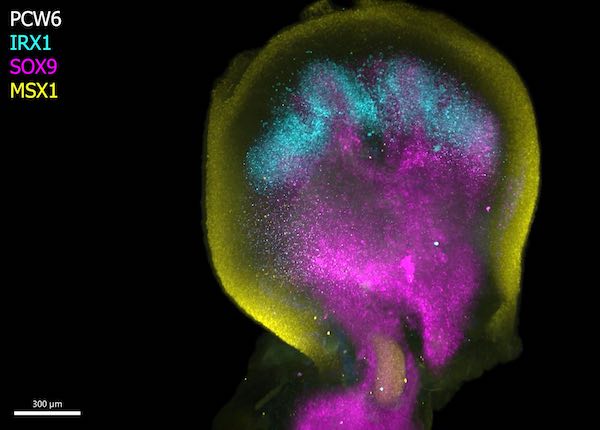

Scientists have uncovered unprecedented insights into the formation of human hands and feet and the intricate processes that govern their development.

This is among many processes captured for the first time as scientists unveil a spatial cell atlas of the entire developing human limb.

Special staining of the tissue revealed clearly how cell populations differentially arrange themselves into patterns of the forming digits.

Limbs are known to initially emerge as undifferentiated cell pouches on the sides of the body, without a specific shape or function. But after 8 weeks of development, they are well differentiated, anatomically complex and immediately recognizable as limbs, complete with fingers and toes.

In this new study, scientists from the Wellcome Sanger Institute, Sun Yat-sen University, and their collaborators analyzed tissues between 5 and 9 weeks of development. This allowed them to trace specific gene expression programs, activated at certain times and in specific areas, which shape the forming limbs.